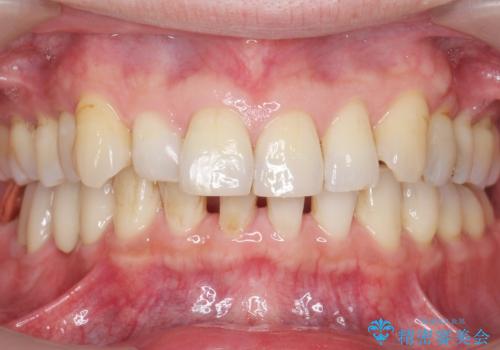

ゴールド(PGA)クラウンの自然な咬み心地とブリッジの審美的な仕上がりに喜んで頂けました。

モチベーションが上がり、ホワイトニングもご希望され補綴前に行いました。

右下⑥5④ブリッジ:オールセラミッククラウン スタンダード